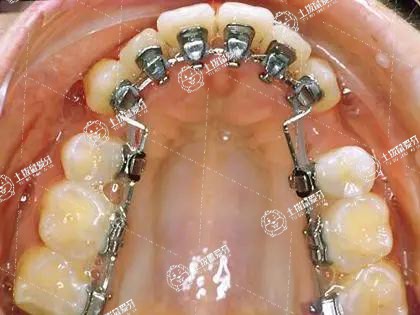

正畸牙齒時(shí)固定矯治器的托槽粘接的太靠近牙齦組織或調(diào)整加力時(shí)力量過大、由于戴矯治器后口腔衛(wèi)生不良引起的牙齦炎等,都可以造成牙齦腫脹。

如果是由于托槽粘接的太靠近牙齦組織刺激牙齦腫脹,需要重新粘接托槽。如果是由于調(diào)整力量時(shí)過大引起牙齦組織腫脹,可以通過減小調(diào)整力量或延長調(diào)整力量的時(shí)間來改善。